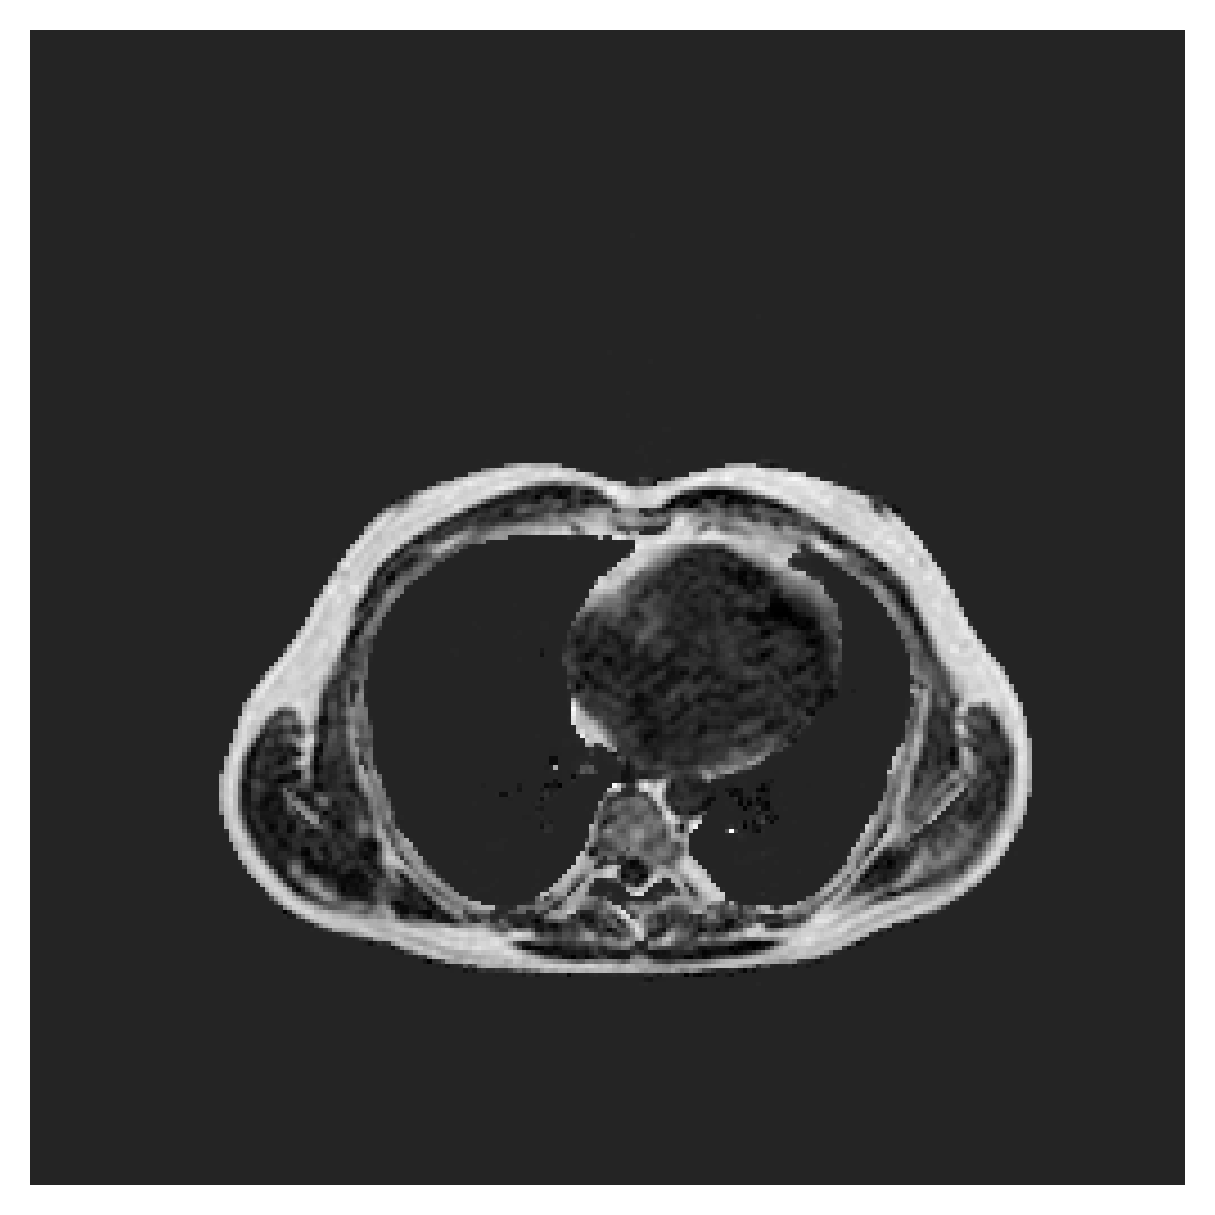

([5]) The Automated Cardiac Diagnosis Challenge (ACDC) is a public benchmark multi-class heart segmentation dataset. It contains cine-MR images of 150 patients (of which 100 are available for training and the rest 50 comprise a test set), covering healthy scans and four types of pathologies in equal amounts, with annotations for the right ventricle (RV), myocardium (Myo) and left ventricle (LV) heart structures. We split the training set randomly, using 65 subjects for training, 10 for validation and 25 as a hold-out test set. Due to the large and varying interslice gap, we work with 2D slices instead of 3D volumes directly. This includes distance map computation.

We normalize the volumes and resize the slices to pixels. As the official dataset comes with full annotations, we create a synthetic point ground truth. This is done by first randomly choosing the centers of the point annotations within the class masks, followed by filling an ellipse with axes lengths of and (in pixels) around each center. The intersections of these elliptic discs with the underlying full annotations are then used as our point ground truth. See Figure 2 for an example of the created weak annotation mask. The point annotations are created for every slice, one for each foreground object present in the slice.

The images contain two channels, one for water and one for fat content. For training, we normalize the volumes (per channel) and use 2D slices in the coronal plane, sized . The weak annotations are created synthetically, following the same procedure as described for the ACDC dataset.